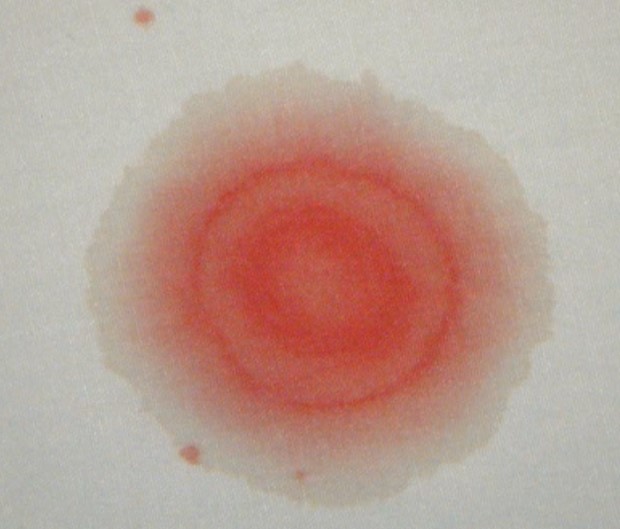

鼻出血に混じって、サラサラとした性状の液体が一緒に流れ出て来る場合があります。

このような場合、鼻出血によって二重のシミが作られます。(double ring sign / halo sign)

このような場合、鼻出血に混じって脳髄液が漏れ出ている可能性があります。つまり頭蓋底骨折などが疑われる非常に危険な状態という事です。